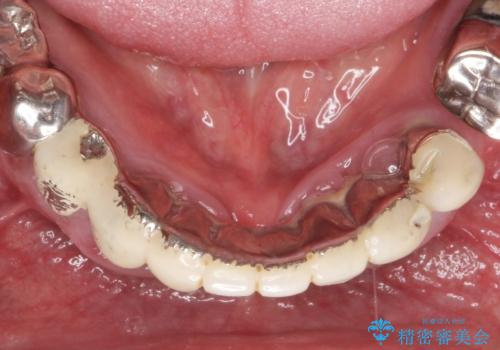

- 被せてある前歯がぐらぐらする、口臭も気になるし、常に歯ぐきが腫れていていることの改善をして欲しい、と来院されました。

歯周組織検査・X線写真検査の結果、重度歯周病であることがわかりました。

残すことのできない歯を抜去し、入れ歯になることを回避すべくブリッジ治療を行いますが支台となる歯の歯周病を改善すべく歯周病により溶けた歯槽骨の再生治療を計画します。